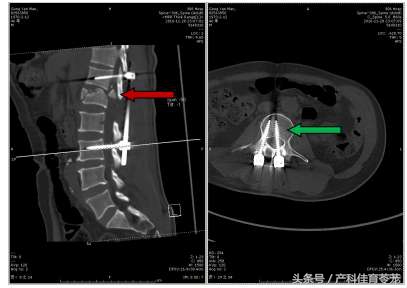

CT可见骨折块仍位于椎管内(红箭),脊髓受压严重;更不幸的是腰3左侧螺钉植入椎管内,加重了神经损伤(绿箭)。

公某高空坠落伤,导致腰1椎体爆裂骨折、脊髓损伤,更不幸的是非洲医疗条件差,手术做错了骨折节段,非但没有去除压迫脊髓的骨块,还破坏了正常脊柱结构,而且钉子打到了神经上,使公某伤上加伤,给下一步手术治疗制造了很大的麻烦。加之路途遥远,公某受伤1个月后才回到祖国,错过了最佳的治疗时机,救治难度很大。